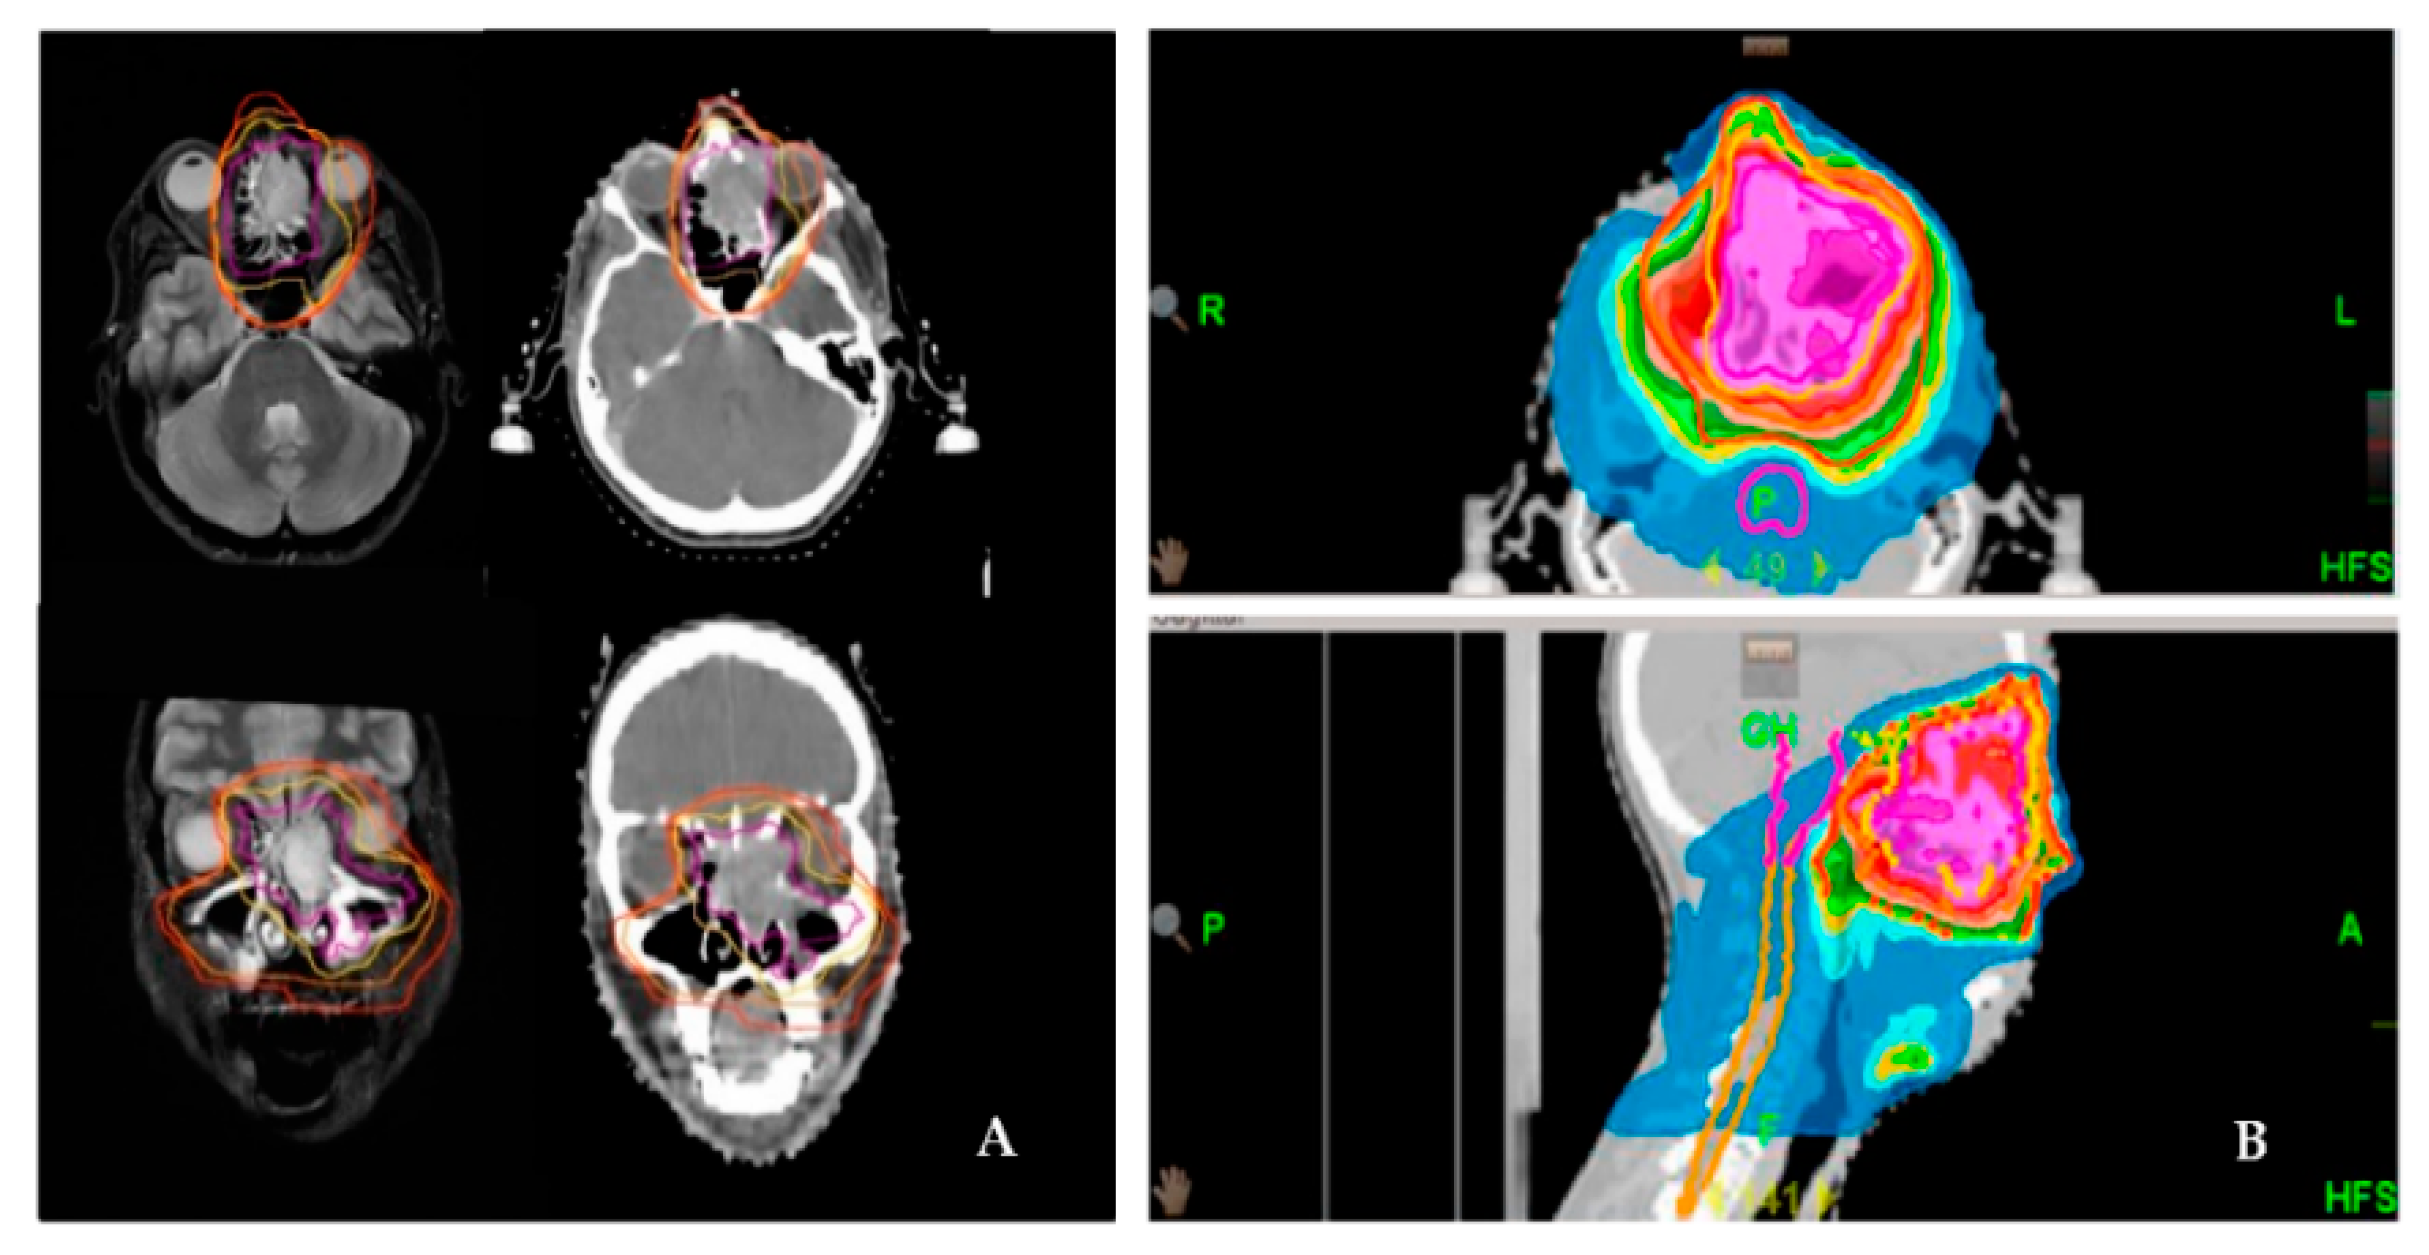

For definitive RT, gross tumor volume (GTV) was defined on planning MRI and contrast-enhanced CT. For adjuvant RT planning, the preoperative and the postoperative images were also coregistered to the planning CT scan. Over the years, two different boost concepts were applied: sequential boost concept (SEQ) and simultaneous integrated boost concept (SIB). For adjuvant treatment, after delineation of the pre-surgery GTV, an isotropic margin of 5 mm for SIB 1 and 10 mm for SIB 2 and 10 mm for SQB by the TPS was deemed as the clinical target volume (CTV1 or SIB1, respectively) was generated. Manual correction on each slice fitted the CTV1/SIB1 to anatomical borders (e.g., bone). For definitive treatment in cases of SIB planning, the SIB2 volume was created by another 5 mm margin around SIB1 (Figure 1). For the planning target volume (PTV) for both radiation settings, a further 5–10 mm and a set-up error of max. 3 mm was generated and manually corrected on each slice. The cervical lymph node levels I-III and retropharyngeal nodes were irradiated only in cases of histologically positive cervical lymph nodes or with macroscopic evidence in definitive situations.

For the SEQ concept, the single dose was 1.8–2.0 Gy to 50 Gy to the PTV, and thereafter, a cumulative dose of 60–66 Gy (postoperative setting) or 66–70 Gy (definitive setting) was applied to the boost volume. The SIB concept consisted of two SIBs for definitive and of one SIB for adjuvant setting. Definitive SIB1 (GTV plus 5 mm) received a single dose of 2.2 Gy to 70.4 Gy, and an adjuvant SIB (pre-therapeutic GTV plus 10 mm) was irradiated with 2.14 Gy to 64.2 Gy. Dmean was normalized to SIB1. The definitive SIB2 (GTV plus 10 mm) was 2.0 Gy to 64 Gy. The adjuvant PTV was irradiated with a 1.8 Gy single dose to 54.0 Gy, and the definitive PTV was 1.7 Gy to 54.4 Gy.

Figure 1. Delineation and dose distribution by helical tomotherapy of a left-sided paranasal carcinoma with orbital involvement. Definitive radiation treatment was performed using a SIB concept on Hi-Art tomotherapy (A). Delineation of the target volume on both CT and MRI scans (magenta: GTV; yellow: SIB-1; orange: SIB-2; red: PTV). (B). Dose distribution as a color wash.